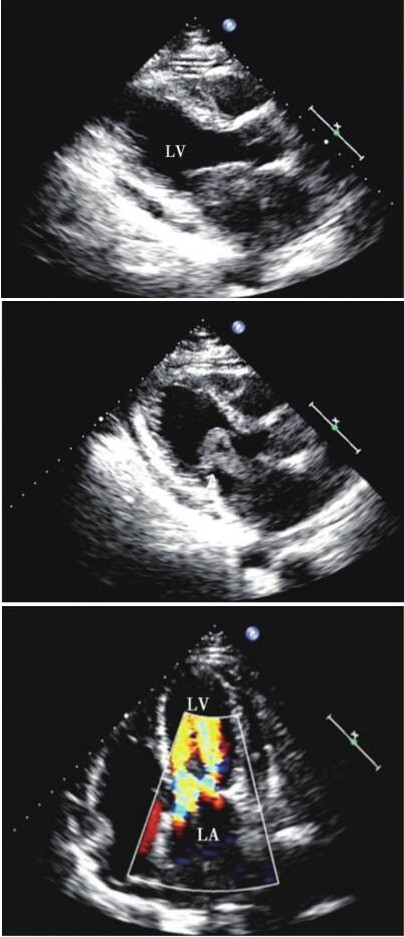

超声心动图:左心房腔内见近圆形较低回声肿物,大小约36mm×58mm,基底部较宽,附着于左心房后壁,几乎填满整个左心房,边缘形态不规则,团块下端随心动周期较规律地在二尖瓣口稍做往返运动,舒张期几乎堵塞二尖瓣口(图80-1),该过程中团块形态变化不明显。诊断:左心房占位性病变 (性质待定),轻度主动脉瓣反流,轻-中度三尖瓣反流,中度肺动脉高压,少量心包积液。因患者左心房异常回声不均匀、边缘欠光滑且基底部较宽,仅肿物下端稍随心动周期活动,同时伴有心包积液,故考虑恶性疾病可能性大,同时左心房黏液瘤不除外,建议外科手术。

图80-1 超声心动图胸骨旁在心室长轴、心尖四腔切面

本例患者在超声心动图诊断过程中主要需与黏液瘤、原发性肿瘤等鉴别,虽然超声心动图所见肿瘤下端稍有类似黏液瘤样活动征象,但该瘤体边缘形态不规则、基底过宽、瘤蒂不明显,随心动周期稍有活动过程中瘤体形态变化不明显,这些均可为临床鉴别诊断提供一定线索。

内膜肉瘤是一种罕见的高度恶性肿瘤,多发生在体循环和肺循环的大血管腔内,超声心动图诊断主要需与黏液瘤、原发性肿瘤等相鉴别。该例患者并非在大血管腔内,而是在黏液瘤好发的左心房内形成附壁占位性病变,容易首先考虑黏液瘤。尽管超声可见肿瘤下端有类似黏液瘤样活动征象,但由于基底过宽、瘤蒂不明显、运动幅度小,并未形成明显“鼠窜样”活动,考虑为肿块与周围房壁组织粘连或浸润所致,且其下端轻度活动时肿块形态变化欠显著,提示该肿块质地较传统意义的左心房黏液瘤硬、弹性差,以上线索均对临床诊疗大有裨益。